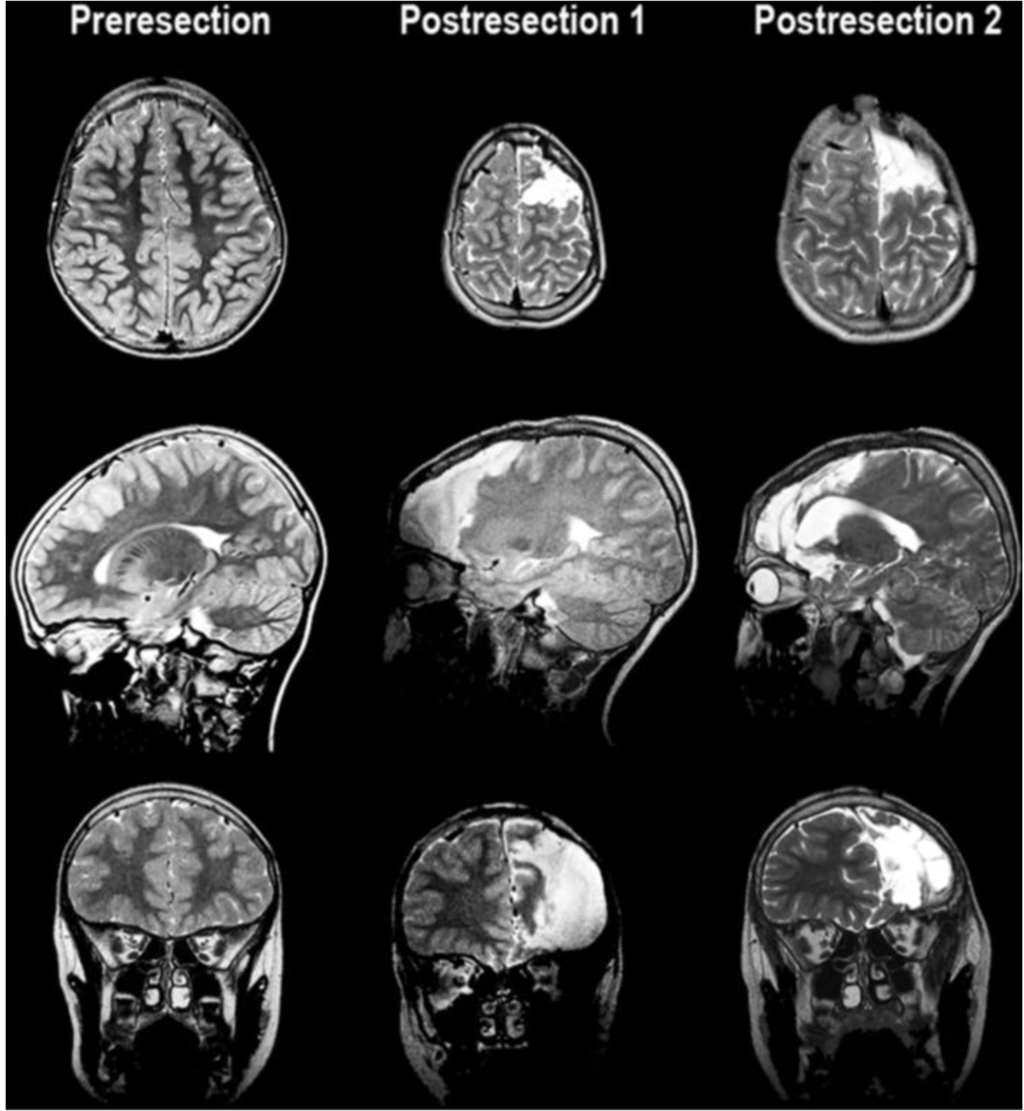

This 14-year-old left-handed male originally presented at two and a half years of life with new onset seizures. Birth was via emergent cesarean section due to fetal bradycardia. APGAR (Appearance, Pulse, Grimace, Activity, Respiration scores of 0–2 each that are summed to assess the health of a newborn with a resulting score range of 0–10, with 7 and above considered normal) scores were six at one minute, and nine at five minutes of life. The patient was reportedly in good health and undergoing normal development until 18 months of age when his first seizure was observed and was characterized by elevation of his right arm. Over the course of the next few months the patient had several more similar episodes, which escalated to include hyperventilation and fits of laughter. Two ambulatory EEGs were performed. The first EEG captured a seizure described as left hemisphere dysrhythmia without spreading. The second EEG did not capture seizure activity but demonstrated interictal epileptogenic regions in the frontotemporal region (F3). Computerized Tomography (CT) scan and Magnetic Resonance Imaging (MRI) of the head were normal (see Figure 1, left column).

Figure 1. MRI images showing pre-resection (left column), and resection cavity following the first procedure (middle column) with resection to the pre-motor gyral bank and second procedure (right column) with resection back to the primary motor area.

Once the primary motor cortex was identified both by direct cortical stimulation as well as phase reversal of cortically evoked responses with median nerve stimulation, the patient underwent his first of two surgical resections with a partial frontal lobectomy sparing the gyral bank of the posterior portion of superior, middle, and the operculum portion of frontal gyrus, just anterior to the primary motor strip [Figure 1 (middle column)]. The white matter tracts were preserved posterior to the resection by respecting the vertical organization of the motor tracts. This resection was carried out with the assistance of intraoperative motor mapping to confirm that the primary motor tracts were spared after the resection through consistent stimulation of the motor hand area. No histopathological abnormality was found upon microscopic examination of the resected tissue.